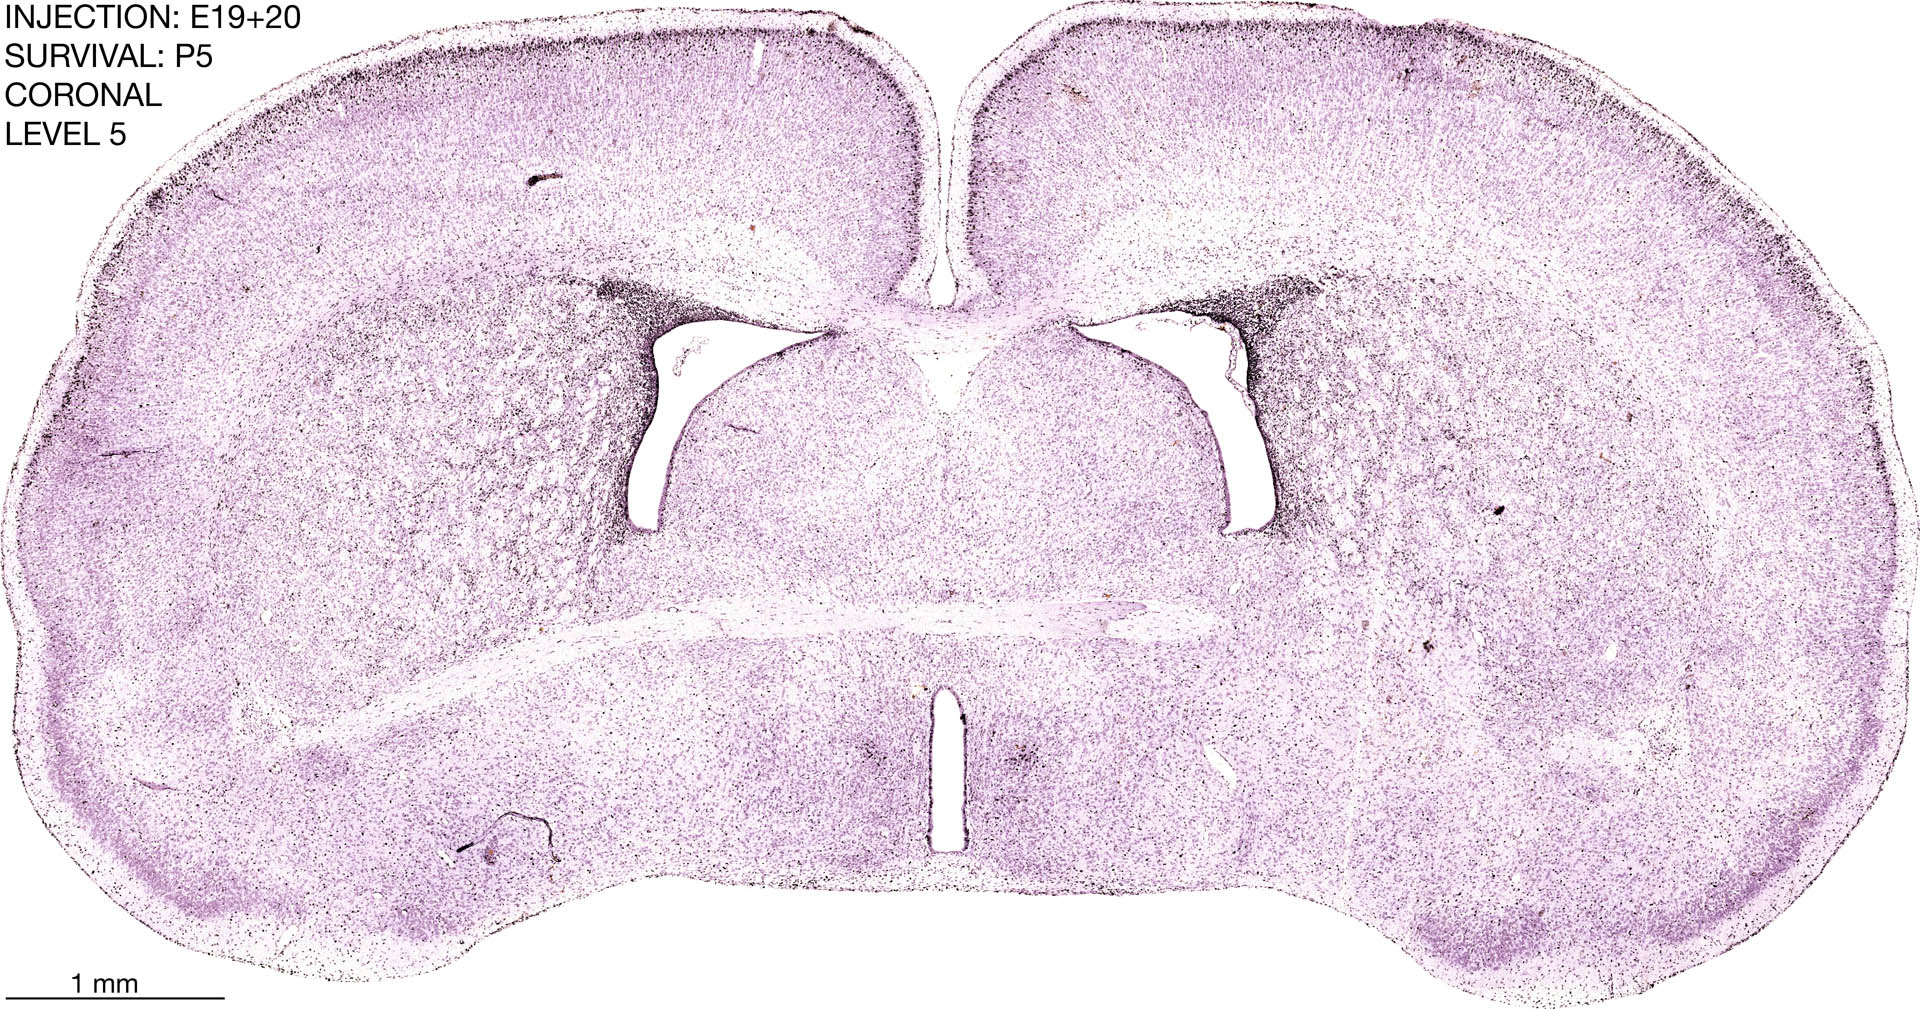

E19+20 P5 Survival The images below are from the brain of a rat that was exposed to tritiated thymidine on E19+20 and survived to P5. Download: Large | High Res Download: Large | High Res Download: Large | High Res Download: Large | High Res Download: Large | High Res Download: Large | High Res Download: Large | High Res Download: Large | High Res Download: Large | High Res Download: Large | High Res Download: Large | High Res Download: Large | High Res Download: Large | High Res Download: Large | High Res Download: Large | High Res Download: Large | High Res Download: Large | High Res Download: Large | High Res Download: Large | High Res Download: Large | High Res Download: Large | High Res Download: Large | High Res Download: Large | High Res Download: Large | High Res Download: Large | High Res Download: Large | High Res Download: Large | High Res Download: Large | High Res